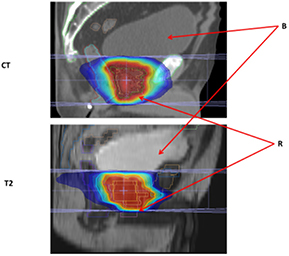

The effects on uniform rED assignment on T2-based plans (T2_D1_B1_O0 and T2_D1_B1_O1) were found to be larger (figures 4(a) and (b)) than the Gold St. When optimization of the pancreas and prostate plans was performed, target coverage was achieved without violating OAR planning constraints; however this does result in larger/smaller difference in OAR doses compared with the Gold St (figures 4(c) and (d)). These large differences in IMRT plan quality metrics was partly due to changes in anatomical shape, volume and position of the organs/tissues in between image acquisitions (figures 5 and 6). However, the DVPs for the OAR still meet the planning criteria in table 1 for both pancreas and prostate IMRT plans (i.e. T2_D1_B1_O1 in tables 10(a) and (b)). The central axis (CAX) of the beams on the T2 images pass through different tissues (i.e. beams3 and 4 in figure 5 pass through different amounts of small bowel, large bowel and NST) with slightly different rED, shape and volume that lead to small changes in absolute dose, which yield very large percent changes compared to the Gold St. For example, panc2's stomach Dmax on the Gold St was 17 Gy and 52.2 Gy on T2_D1_B1_O0 (a +183.4% difference but still clinically acceptable). Optimization of the panc2 plan reduced the stomach Dmax to 51.9 Gy, which is within clinically acceptable limits but still a +178.8% difference. A similar observation was made on prost1, where the bladder Dmean on the Gold ST were 9.2 Gy but increased to 12.7 Gy (+37.7% difference) on T2_D1_B1_O1. Re-optimization on the T2 reduced the bladder mean dose to 9.62 Gy, which is clinically acceptable but still 4.1% higher than the Gold St. Additional examples of large increases in DVP that remain within clinical acceptable range in table 1 include the 6% increase in rectum V45, which is a difference of 22.5% and 28.6% between Gold St and T2_D1_B1_O1, respectively.

Standard image High-resolution imageFigure 6. Prostate CT and T2 images. Abbreviations: CT—sagittal view through isocenter on prostate IMRT CT data set; T2—sagittal view through isocenter on prostate IMRT T2 data set; B—bladder and R—rectum.

Download figure: